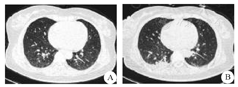

患者 女,55岁,因"畏寒发热4 d"于2017年11月13日在家人搀扶下步入中国医科大学人民医院急诊科就诊。患者发病前4 d曾有受凉发热史,体温最高达39 ℃,伴咳少量白色粘痰。既往体健,无近期疫苗接种史,否认外伤史、冶游史及自身免疫性疾病史。急诊体检:体温39.6 ℃,双肺呼吸音粗,心律齐,心率106次/min,腹部无压痛;意识清楚,颅神经未见异常,双侧巴宾斯基征阴性,颈软。肺CT扫描显示:双肺纹理紊乱,肺内散在小结节及陈旧性病变,未见明显急性炎症改变(图1A)。血液常规显示白细胞计数正常,中性粒细胞比例78.9%(↑),C反应蛋白正常。以"发热待查"收入呼吸内科住院。入院后给予头孢西丁抗炎和物理降温治疗,体温波动于38.3~41.1 ℃,并相继出现排尿、排便困难。入院1周后病情继续进展,表现为咳嗽无力、呼吸困难,以至呼吸衰竭、精神萎靡,复查肺CT显示双肺下叶模糊淡片影,右肺下叶不张可能性大,双侧胸腔积液,考虑与吸入性肺炎有关(图1B)。因患者呼吸困难继续加重,故转入ICU病房,行药物治疗的同时予以呼吸机辅助通气。期间患者体温仍持续在38 ℃以上,并反复达40 ℃,故在给予抗菌素治疗的同时又相继给予奥司他韦、更昔洛韦抗病毒治疗,并更换静脉抗菌素为万古霉素1500 mg/d、泰能4 g/d。但患者仍持续高热不退,期间多次进行血液常规化验,显示白细胞总、分数均轻度异常或正常;降钙素原0.07 ng/mL(参考值<0.05 ng/mL);肝肾功能、甲功五项、凝血功能、乙丙型肝炎、肿瘤标志物未见异常。血液病原微生物学检查:布氏杆菌、人类免疫缺陷病毒、巨细胞病毒IgM、单纯疱疹病毒IgM、军团菌IgM、柯萨奇病毒IgM均为阴性,支原体抗体滴度、肥达氏反应和外斐氏反应均无异常。免疫学检查:抗中性粒细胞胞浆抗体(-);抗核抗体谱(15项)中抗SS-A抗体(±)、抗Ro-52抗体(±);血沉、风湿三项、血IgA、IgG、IgM、IgE及血清蛋白电泳均未见明显异常。血培养:未见需氧、厌氧菌生长。痰涂片:无细菌、结核杆菌生长。尿常规、尿沉渣定量无异常。心脏超声、全腹CT扫描无异常。入院第11天(2017年11月24日)因停用镇静药物后患者仍呼之不应,急请神经内科会诊。脑脊液检查:脑脊液压力160 mmH2O(1 mmH2O=0.098 kPa),外观无色透明;脑脊液常规:白细胞总数352×106/L(↑),未见红细胞;脑脊液生化:糖2.34 mmol/L(↓)、蛋白质0.78 g/L(↑)、氯化物正常;细菌及结核杆菌涂片(-)。血液及脑脊液水通道蛋白和脑脊液寡克隆带未检测。因患者脑脊液白细胞总数增高较明显,故给予抗菌素治疗的同时给予静脉甲泼尼龙(500 mg/d、连续4 d,后逐渐减量)治疗。激素治疗的第2天患者体温开始下降,第5天降至正常,第9天自主呼吸明显恢复,但仍咳痰无力。在患者呼吸困难、发热症状好转的同时,也发现患者存在四肢瘫痪(双上肢肌力Ⅱ级、双下肢肌力Ⅰ级)。为进一步明确肢体瘫痪原因,入院4周后(2017年12月7日)行头颅MRI平扫,显示脑干、双侧丘脑、双侧小脑半球、双侧半卵圆中心、侧脑室旁及基底节区多发、不对称的异常信号(图2)。2017年12月14日颈段MRI平扫显示:延髓与颈髓交界、C1~T1节段间多发、不连续的髓内异常信号(图3)。结合患者发热、亚急性起病过程,尽管脑脊液呈炎性改变,但给予抗病毒、抗细菌治疗效果不佳,并结合中枢神经系统影像学改变,即颅内及脊髓均有受累,支持中枢神经系统脱髓鞘性疾病的诊断。2017年12月24日患者自主呼吸完全恢复,此期间排便功能及肌力也逐渐恢复,于2017年12月28日转回呼吸内科病房。出院后随访3个月,患者仍处于恢复中,双上肢肌力Ⅴ-级、双下肢肌力Ⅳ级,因遗留排尿困难仍予留置导尿管。

A:双肺纹理紊乱,肺内散在小结节及陈旧性病变;B:双肺纹理增强及下叶可见模糊淡片影,右肺下叶不张可能性大,双侧胸腔积液